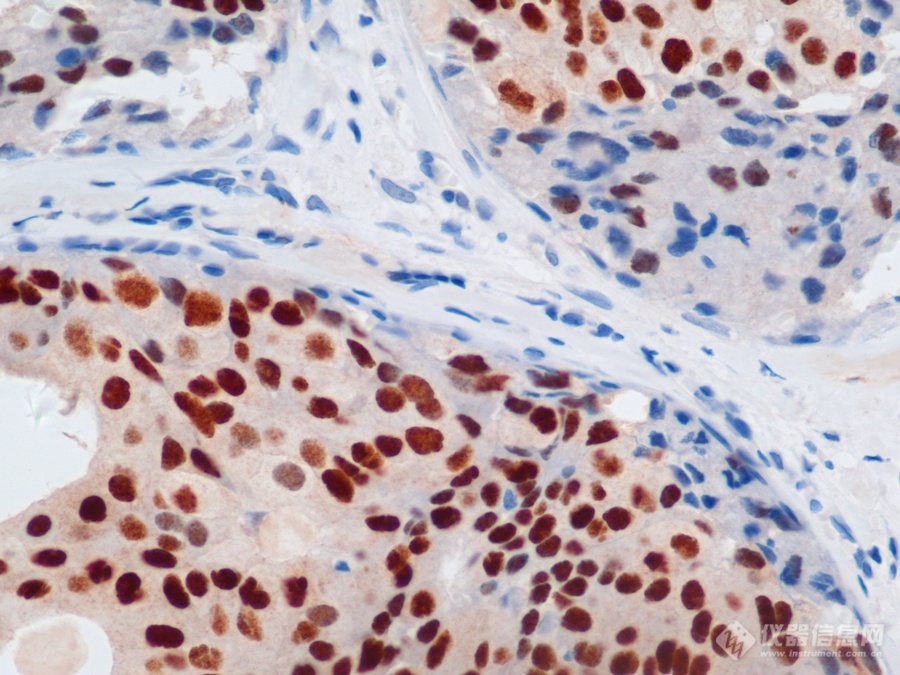

应用类似原理,还有不使用荧光染色的免疫组化(IHC)染色,主要用于尸检研究,判断病毒对身体各器官的感染情况,比如猴痘病毒能找到相关研究。

IHC免疫组化染色,猴痘病毒感染犬的支气管(红色为病毒反应)